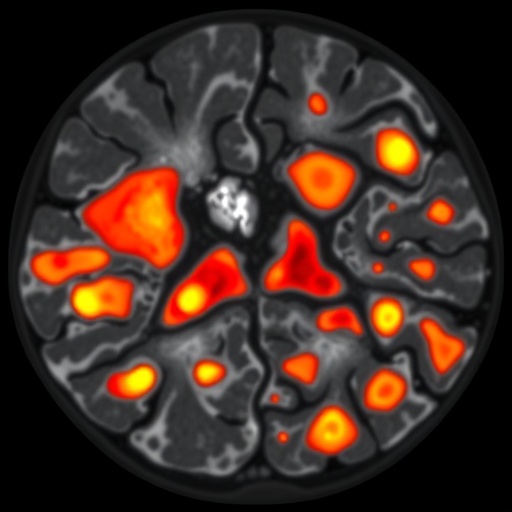

Central to their discovery was the identification of seven distinct microenvironments or “niches,” each characterized by a unique cellular composition and communication network between malignant B cells and various immune cell populations. These niches ranged from immune-depleted zones dominated by tumor cells to highly inflamed regions where immune cells, especially T lymphocytes, infiltrate robustly and show signs of activation. Intriguingly, tumors developing in immune-privileged sites—areas normally shielded from immune attack, such as the central nervous system—exhibited a remarkable paradox: despite their immune-privileged status, these tumors harbored a dense population of T cells deeply interspersed with malignant B cells, alongside gene expression signatures indicative of T cell activation and cytotoxic potential.

This revelation challenges traditional concepts that immune-privileged tumors are completely isolated from immune surveillance. Instead, it suggests that these tumors cultivate active immune microenvironments wherein T cells are poised to recognize and potentially attack tumor cells, although the mechanisms enabling tumor evasion and survival remain to be elucidated. These findings also highlight the importance of spatial context in tumor immunology; understanding where and how immune cells interact with cancer cells within the anatomical landscape is critical to interpreting their functional roles and therapeutic potential.

The study’s meticulous dissection of DLBCL’s cellular architecture underscores why patients with seemingly similar tumors often experience vastly different clinical outcomes. Each microenvironment represents a distinct battleground where tumor cells and immune components engage in a complex dialogue, influencing tumor progression or regression. This heterogeneity likely contributes to the varied therapeutic responses observed with standard chemotherapy and emerging immunotherapies. Consequently, targeting only the malignant B cells without considering the supportive or suppressive immune milieu may fall short of achieving durable remissions.